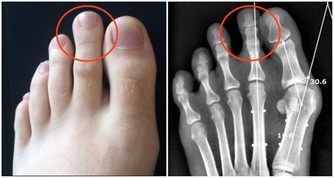

一方面,習慣性的便秘看似危害不大,但長期有毒物質存留於腸道中,會增加腸道腫瘤發生的風險;而另一方面,便秘又可能是腸癌的一個早期信號,這是因為腸道腫瘤的生長,阻礙了糞便的通過,所以才更有可能出現便秘的情況。

總之,排便這件事雖然是很多人不太看重的一件小事,但是和我們的腸道以及身體的整體健康關係密切,應該早點重視起來。排便越是有規律和暢通,患上腸癌的風險會越小。